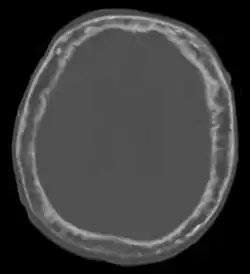

![]() | |

| "This 92 year-old male patient presented for assessment of sudden inability to move half his body. An incidental finding was marked thickening of the calvarium. The diploic space is widened and there are ill-defined sclerotic and lucent areas throughout. The cortex is thickened and irregular. The findings probably correspond to the 'cotton wool spots' seen on plain films in the later stages of Paget's disease." | |